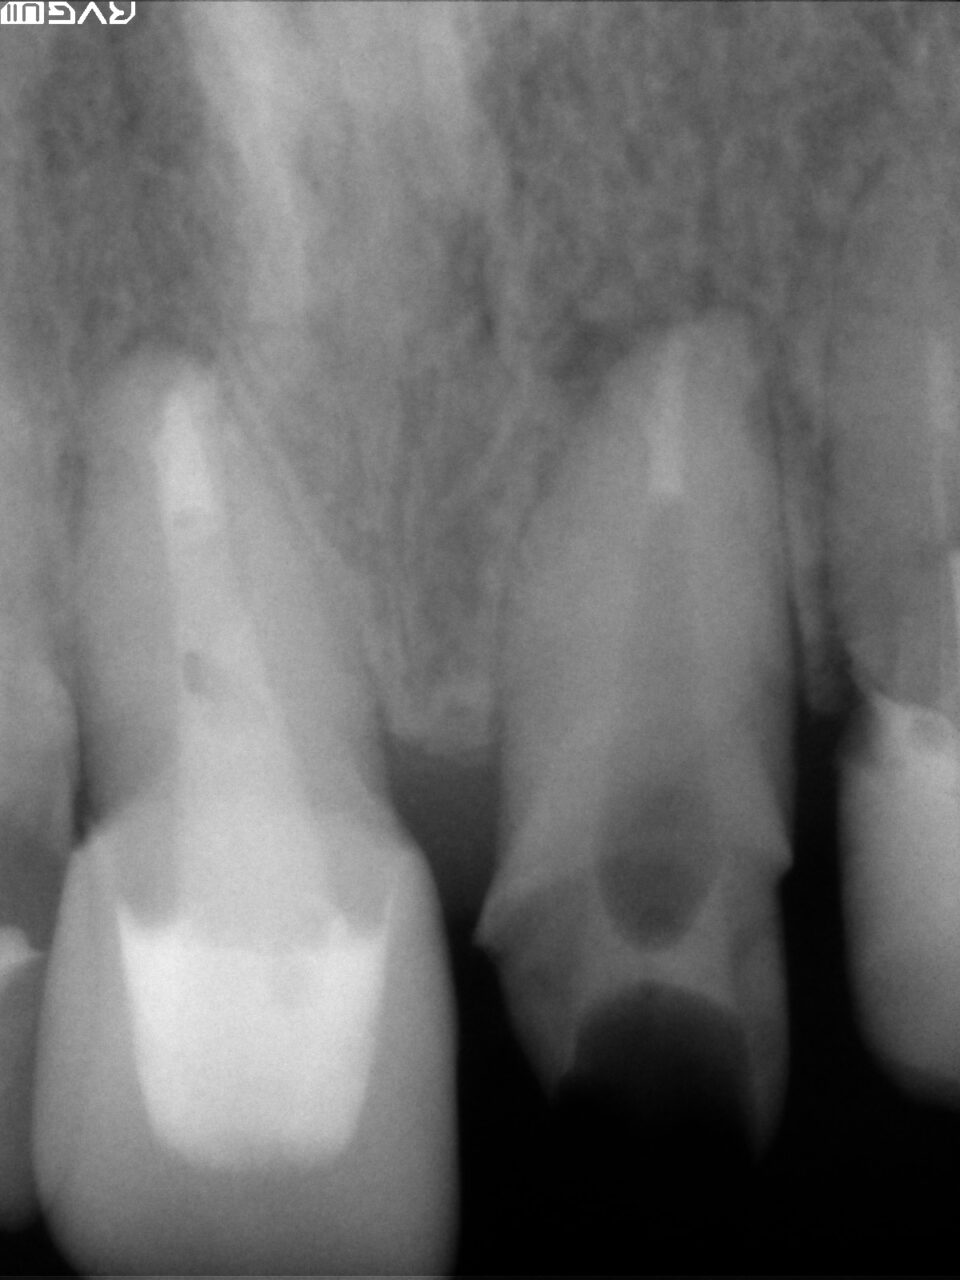

根管形成後、十分に根管洗浄を行いバイオセラミックにて根管充填をしました。

根尖まできちんと根管充填材であるバイオセラミックが入っている事が確認できます。(根管充填後のレントゲン写真)